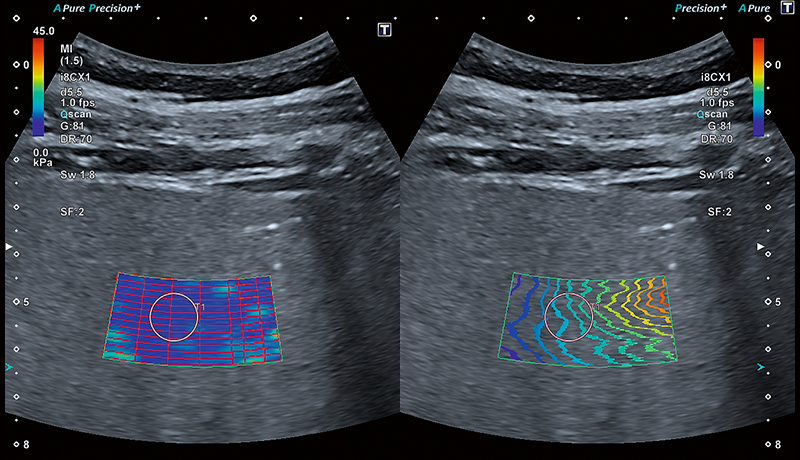

Інноваційна візуалізація дисперсії зсувної хвилі (SWD), яка наразі проходить клінічну оцінку, дозволяє картувати поширення зсувної хвилі для ізольованої оцінки в'язкості паренхіми. Кольорове відображення може надати цінну додаткову інформацію, яка допоможе у подальшому веденні пацієнта.

Залежно від ступеня фіброзу, паренхіма печінки демонструє підвищену віскоelasticity (в’язкопружність). Клініцисти досліджують жорсткість печінки як один із показників для діагностики фіброзу або цирозу печінки. Жорсткість печінки можна виміряти за допомогою еластографії зсувної хвилі (SWE).

Розумні карти допомагають візуалізувати поширення зсувної хвилі в режимі реального часу. Унікальна карта поширення від Canon – це потужний та інтуїтивно зрозумілий інструмент для візуальної оцінки якості еластограми.